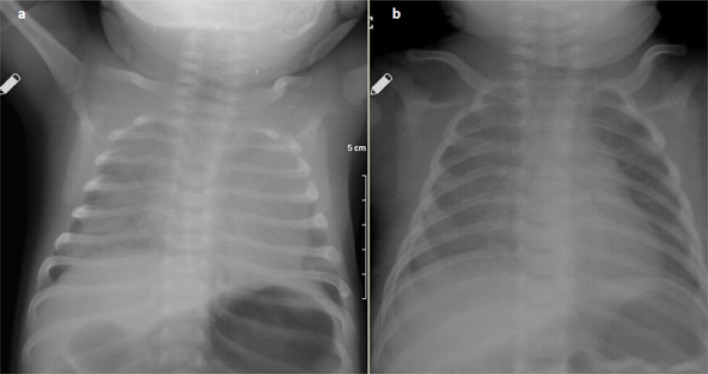

Acute respiratory failure is an important reason for pediatric intensive care admissions. Lung parenchymal disease, airway obstruction, or neuromuscular dysfunction are the most common causes. Negative pressure pulmonary edema, characterized by pulmonary edema associated with upper airway obstruction, can rarely cause sudden onset respiratory failure. Herein, we describe an infant who suffered sudden onset respiratory failure and pulmonary hemorrhage while being held facedown for a bath, was admitted to the pediatric intensive care unit, intubated and mechanically ventilated for three days, and was diagnosed with negative pressure pulmonary edema, and discharged without any sequelae. Negative pressure pulmonary edema is a rare entity. Its true frequency is not known due to the lack of awareness. This report aimed to increase clinician familiarity with negative pressure pulmonary edema in patients with sudden onset respiratory failure and/or pulmonary hemorrhage.